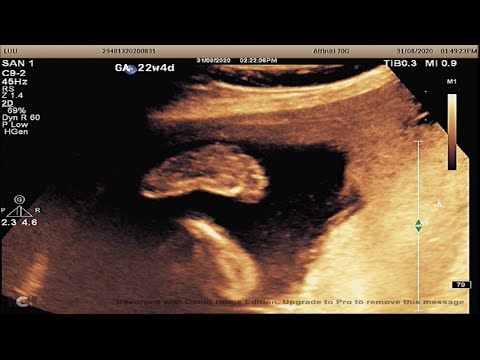

Những điều mẹ bầu cần lưu ý khi thai bị giãn não thất bên

Trẻ em bị giãn não thất thường với triệu chứng: vòng đầu tăng nhanh, đau đầu, chán ăn, hay ói mửa, thay đổi hành vi và tính cách, thay đổi thói quen, suy giảm trí tưởng, mất tập trung, mỏi mệt, thất đ